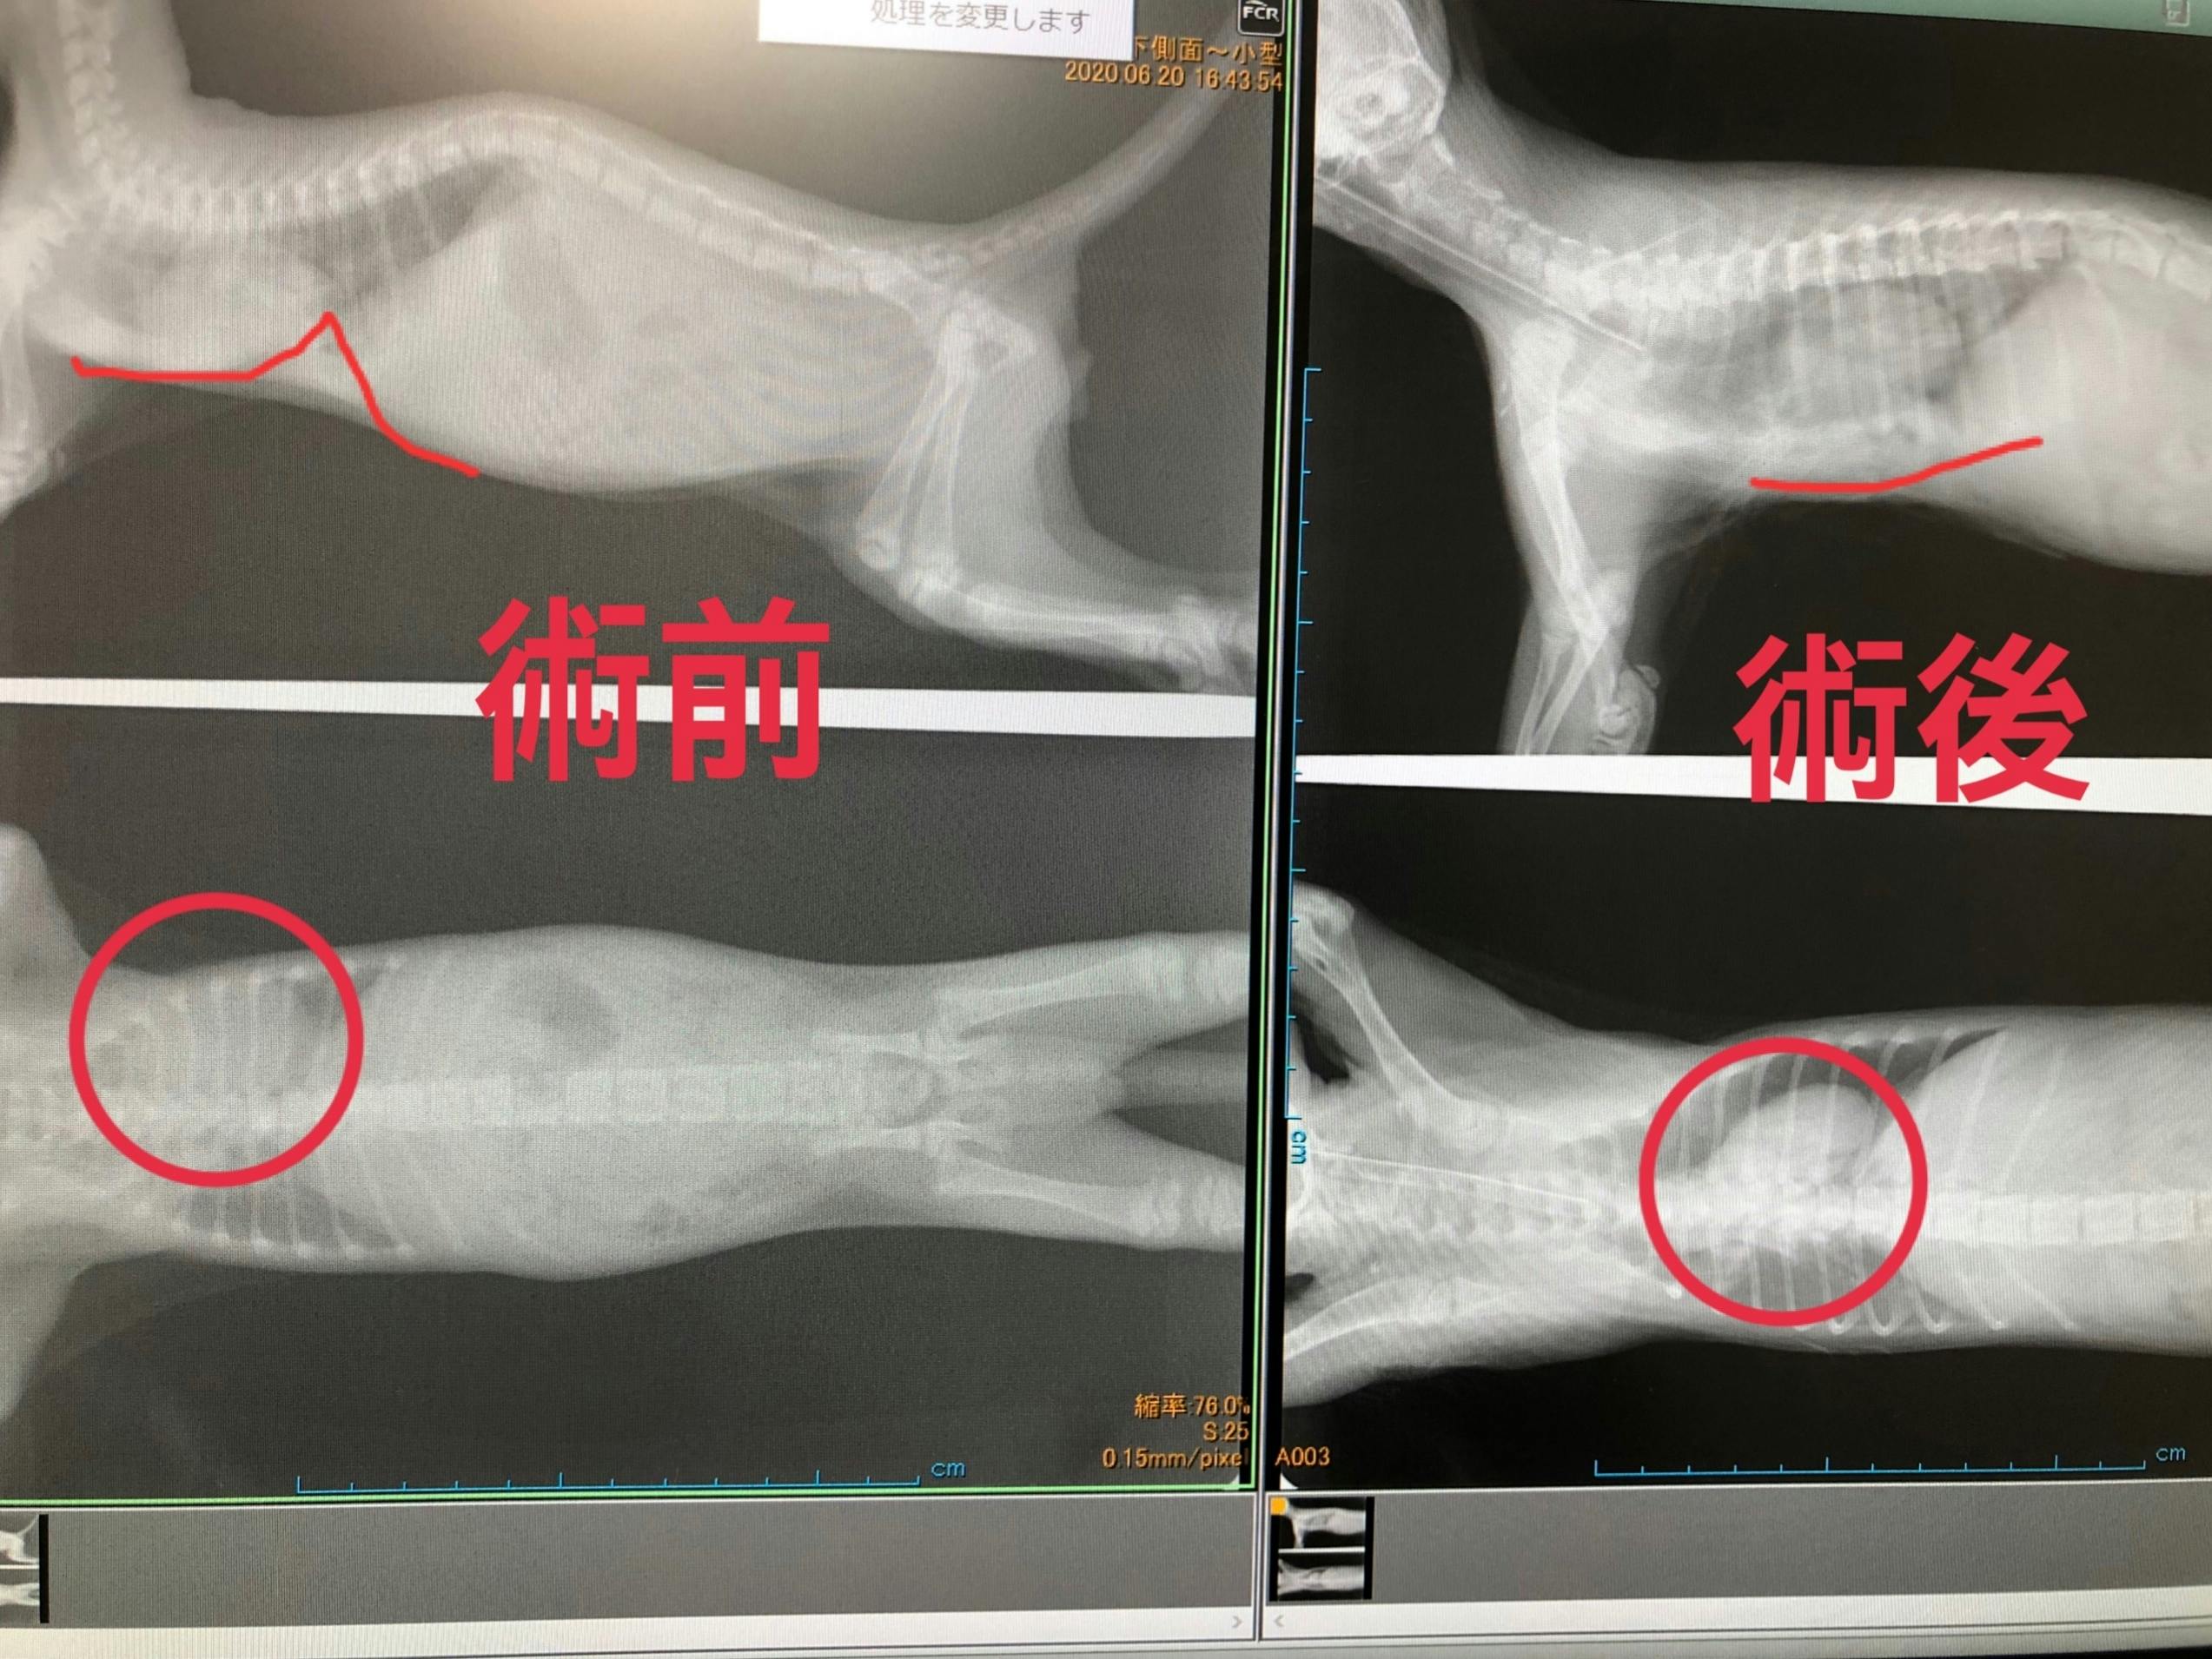

更にコロ助ちゃんは胸部肋骨が陥没している【漏斗胸】という病気を持っていました。

【漏斗胸】というのは遺伝性のある病気で、肋骨が心臓の方へ食い込んでしまい、呼吸が苦しくなってしまう病気です。

身体が成長しきる前にへこんだ胸骨を手術で引っ張る手術が必要ですが、手術に耐えるためには900gを超えなければ厳しいという診断だったので、預かりBABAさんが病気のせいもあって成長がとても遅いコロ助ちゃんに毎日せっせと高カロリー食を食べさせてくれて、ようやく手術に耐えられそうな体重になったので、先日最終検査をして2時間半を超える手術を乗り越えてくれました。

これがコロ助ちゃんの手術前と手術後のレントゲン写真です。

鋭角に食い込んでいた骨がほぼ平らになり、骨に阻害されていた心臓も本来の位置に近くなっています。

遊んでいても少し走るとすぐに口の中もお腹も紫色になりチアノーゼを起こしていたコロ助ちゃんですが、1ヶ月の安静という試練はあれどきっと元気になってくれると思います。